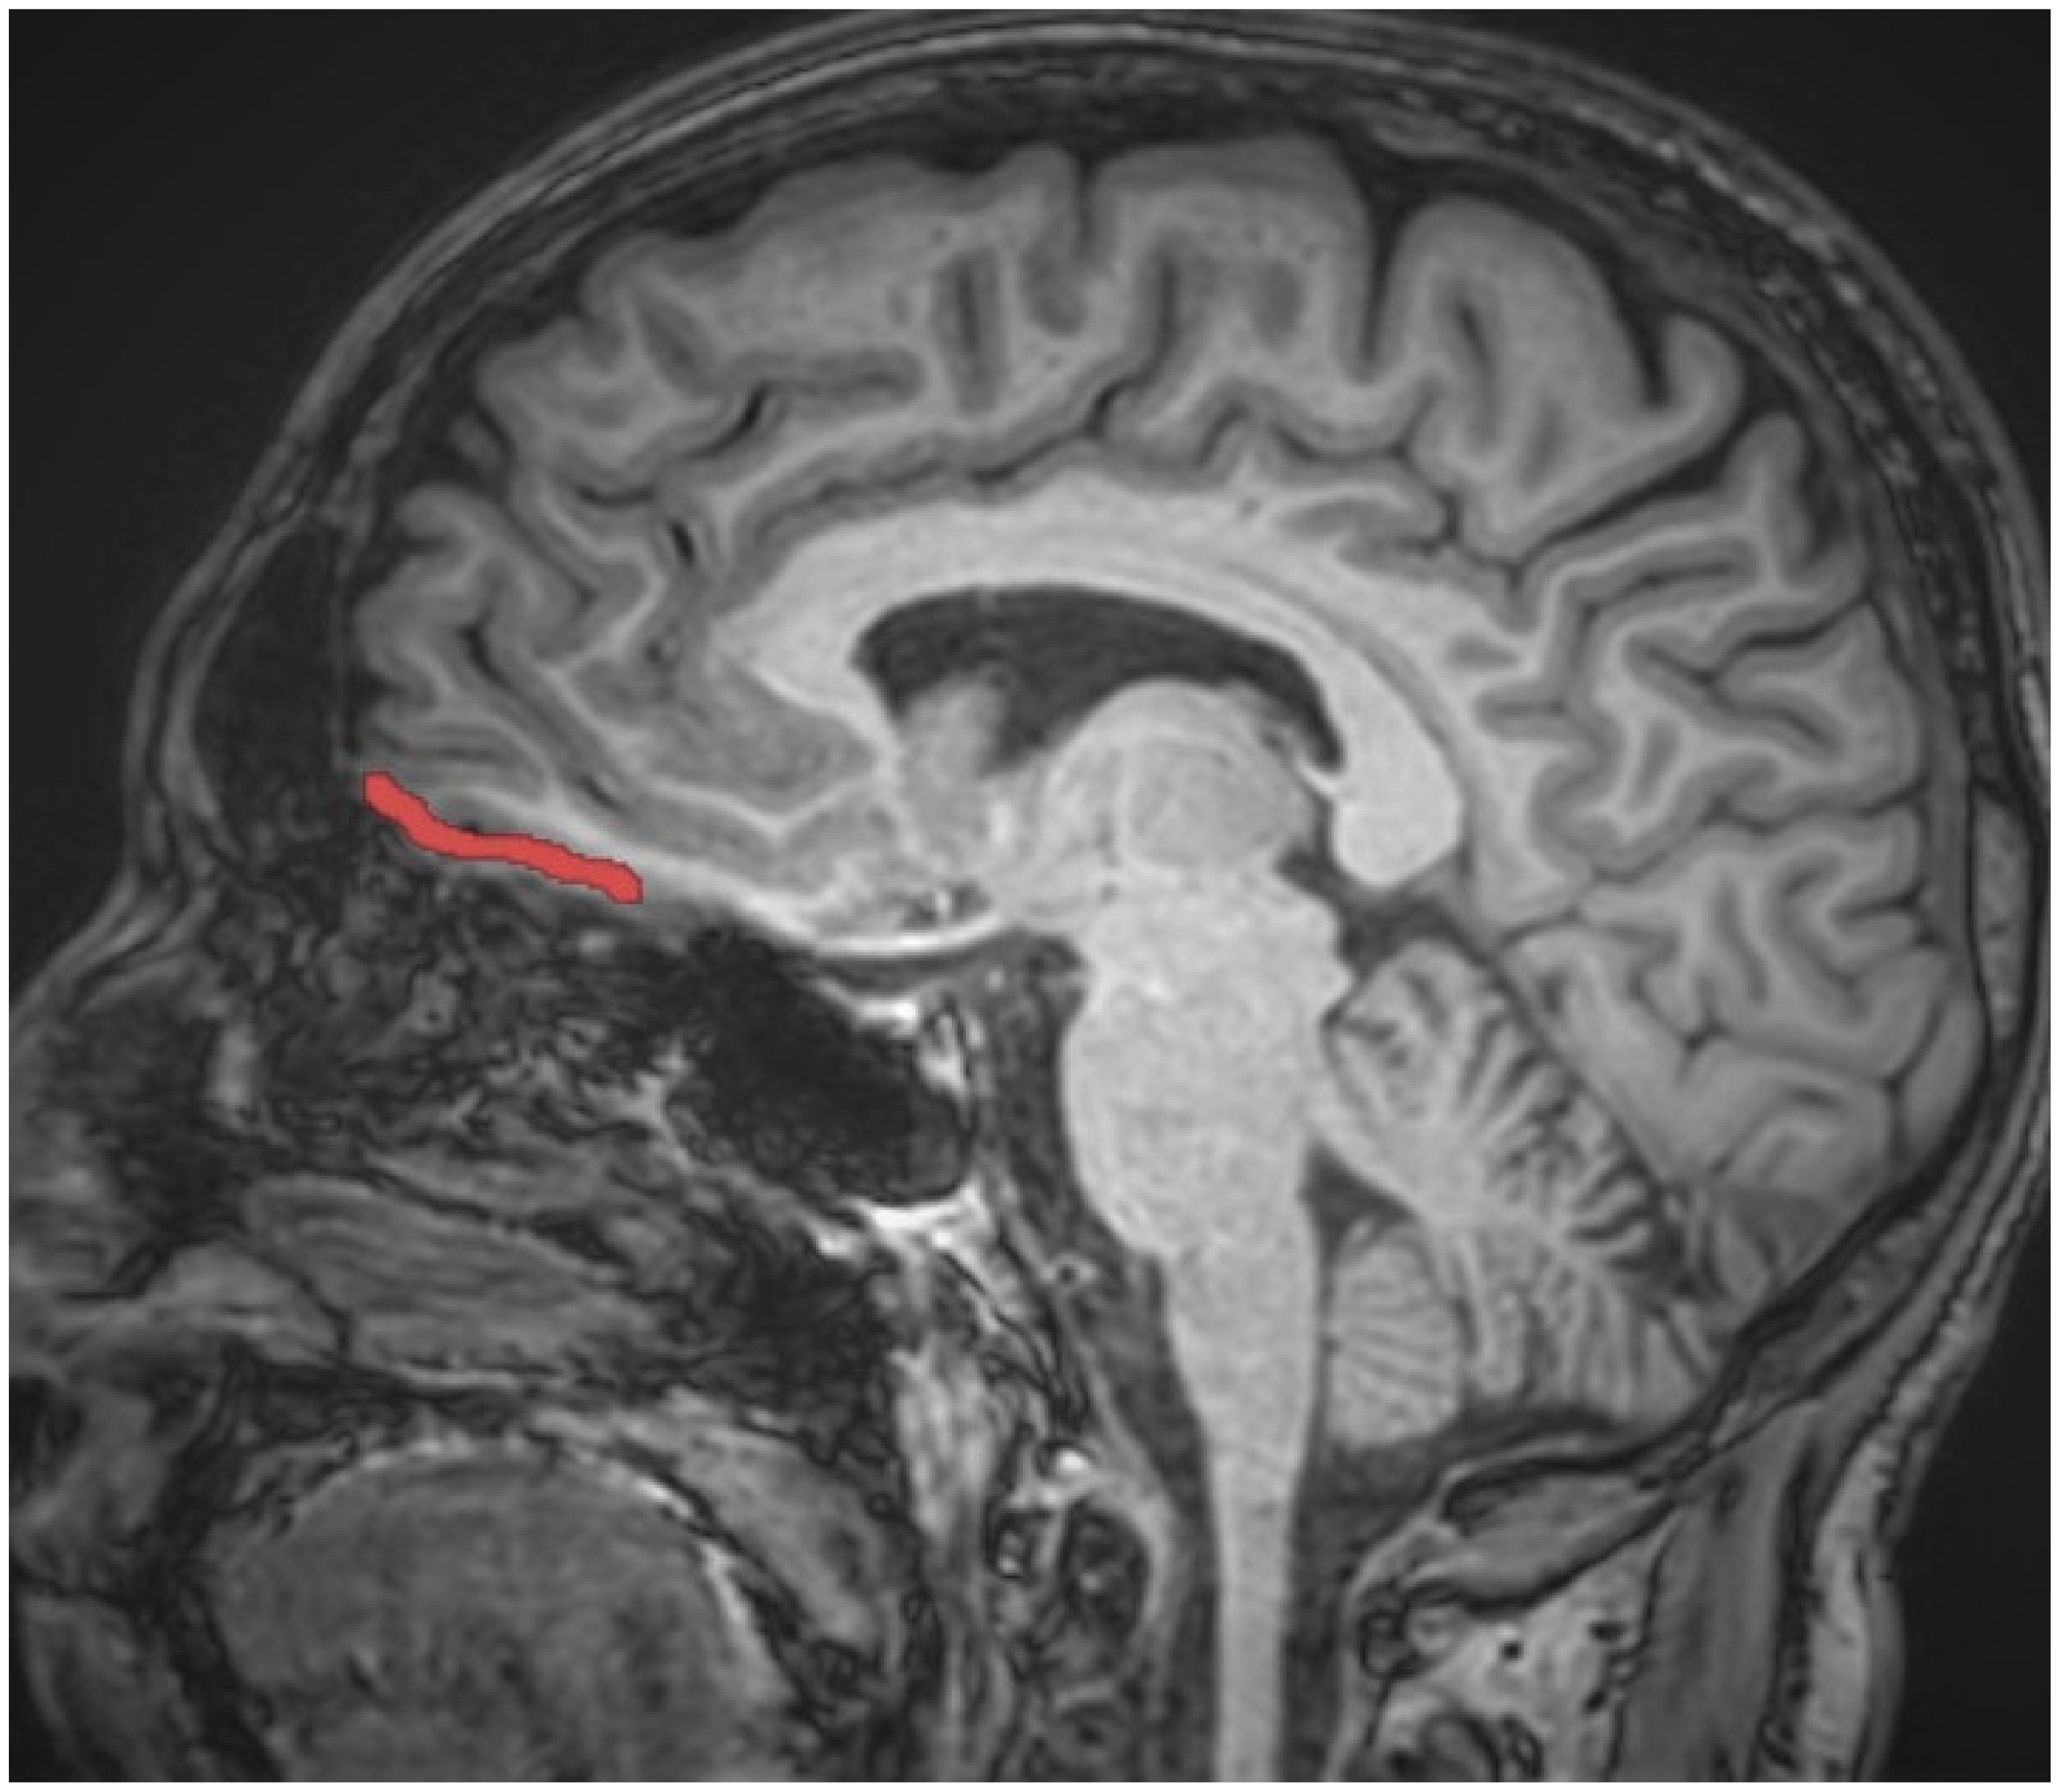

2.2. Magnetic Resonance Imaging (MRI) Procedure

- Yuh, W.T.C.; Afifi, A.K.; Tali, E.T. MRI of Head & Neck Anatomy; Churchill Livingstone: London, UK, 1994; ISBN 0443088926. [Google Scholar]

- Jackson, G.D.; Duncan, J.S. MRI Neuroanatomy: A New Angle on the Brain; WB Saunders Company: New York, NY, USA; Churchill Livingstone: London, UK, 1996; ISBN 0443045437. [Google Scholar]

- Patel, V.H.; Friedman, L. MRI of the Brainnormal Anatomy and Normal Variants; W.B. Saunders Co., Ltd.: Philadelphia, PA, USA, 1997; ISBN 072166945X. [Google Scholar]